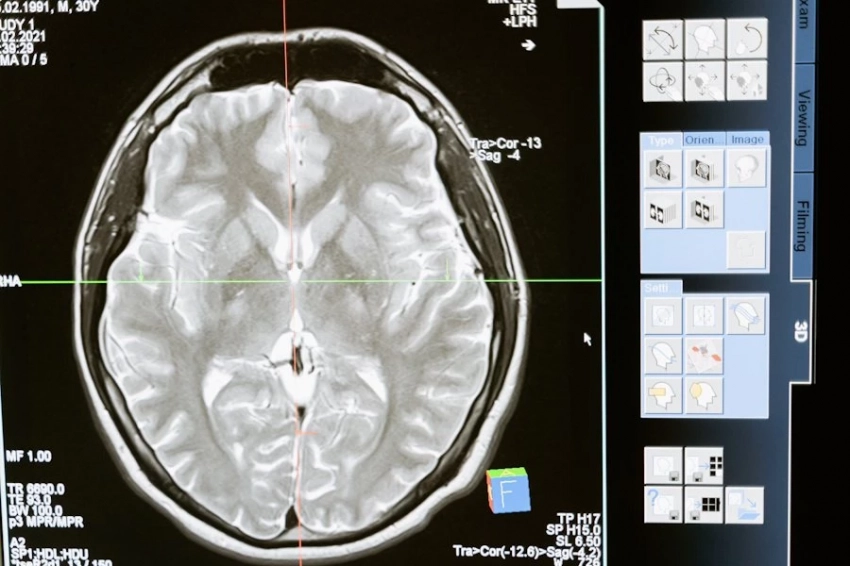

Согласно исследованию, МРТ-сканирование показало, что у людей с заболеваниями десен наблюдаются измененные связи между различными областями мозга по сравнению с людьми с хорошим здоровьем зубов.

Исследователи утверждают, что у людей с заболеванием десен средней и тяжелой степени наблюдались изменения в связях между различными областями мозга и внутри них. В целом, заболевания десен были связаны с нарушением работы нейронных сетей в головном мозге.